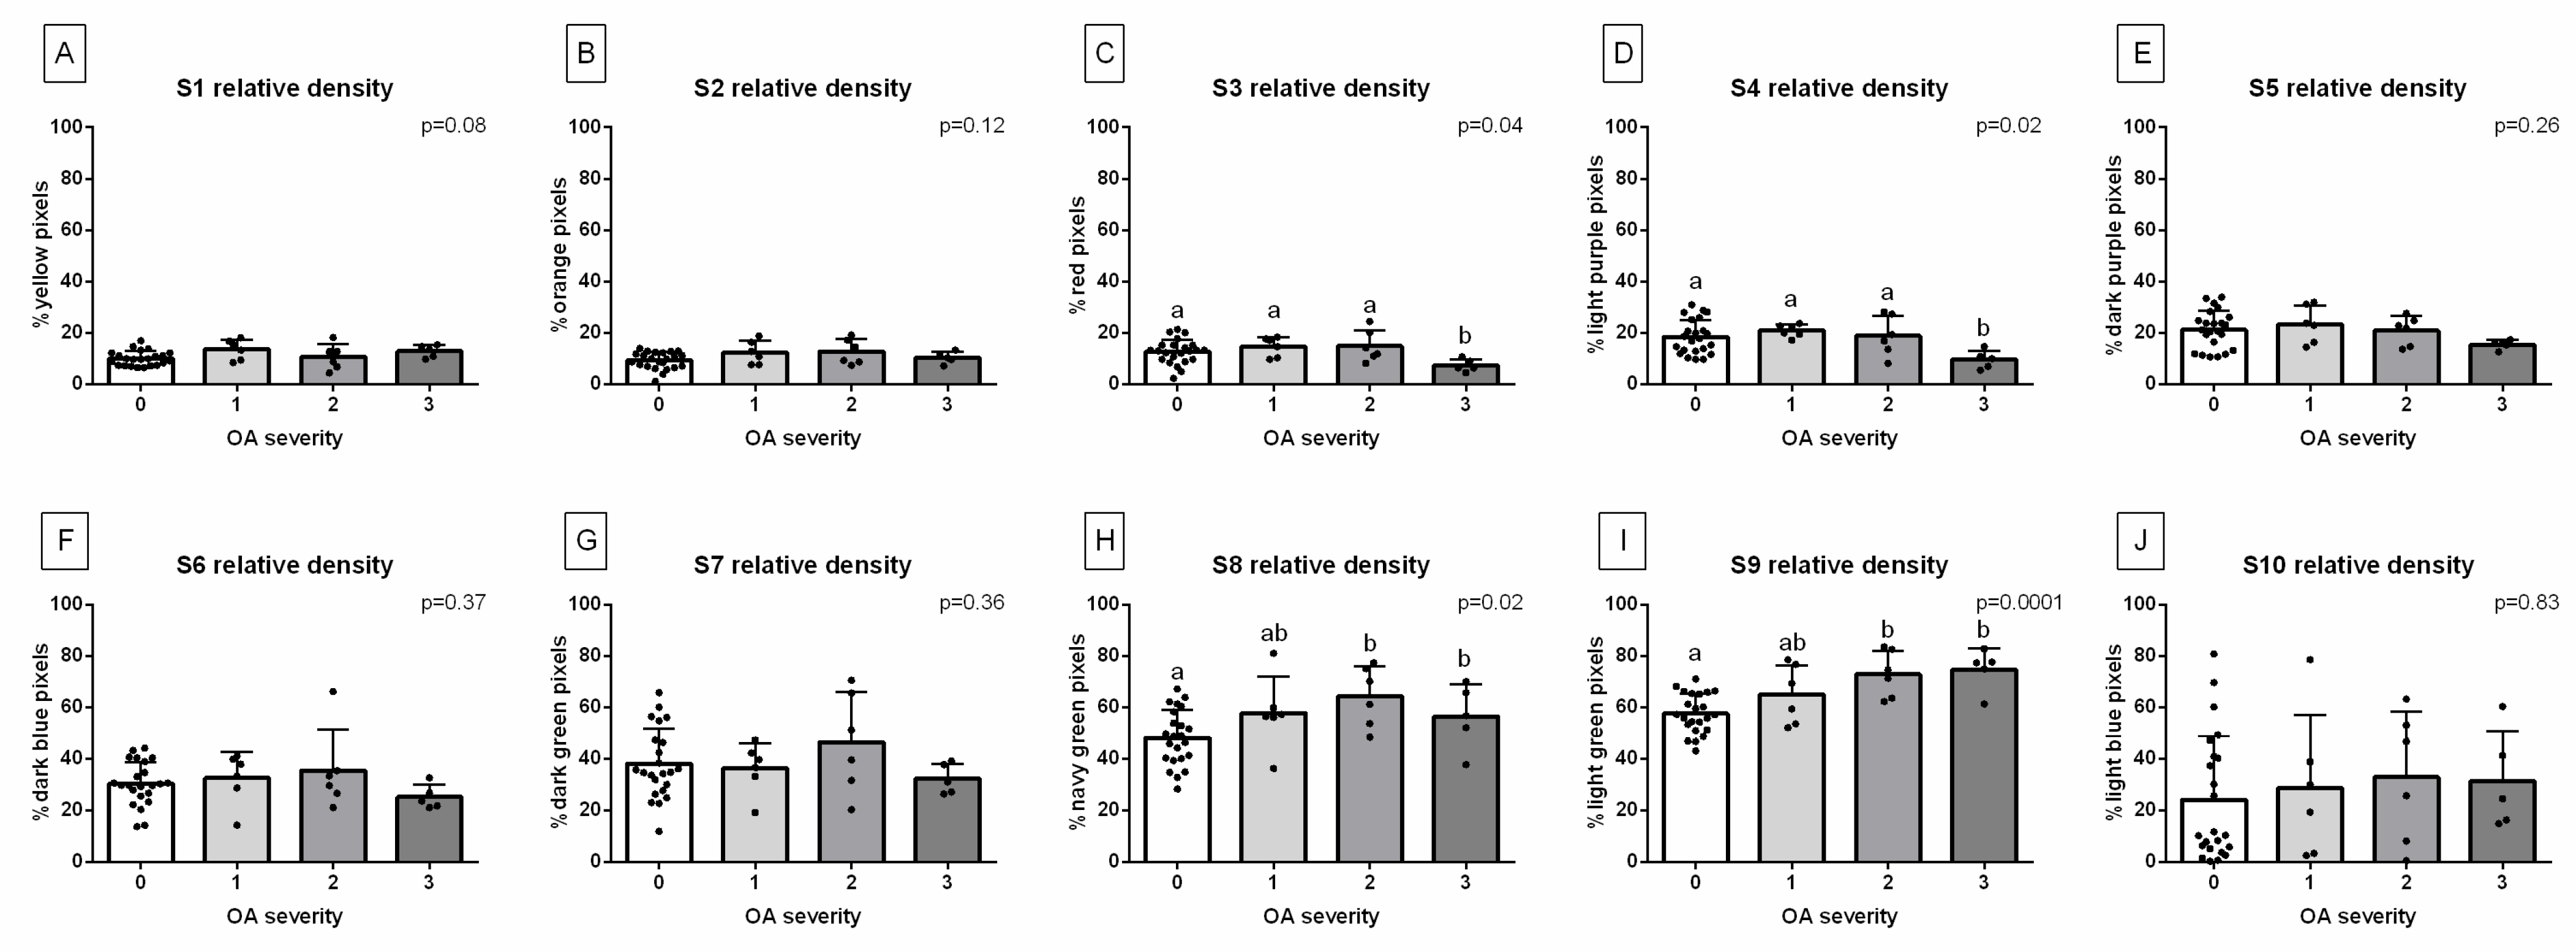

3. Results

| Decomposition | S1 | S2 | S3 | S4 | S5 | S6 | S7 | S8 | S9 | S10 |

|---|---|---|---|---|---|---|---|---|---|---|

| Relative density (HU) | 1009 ± 163 | 1212 ± 111 | 1407 ± 98 | 1600 ± 134 | 1804 ± 112 | 2011 ± 99 | 2204 ± 107 | 2400 ± 133 | 2607 ± 129 | 2803 ± 147 |

| Color | Yellow | Orange | Red | Light purple | Dark purple | Dark blue | Dark green | Navy green | Light green | Light blue |

| HEX code | #FFFF00 | #E08000 | #FF0000 | #E080C0 | #800080 | #0000FF | #008000 | #808000 | #00FF00 | #A6CAF0 |